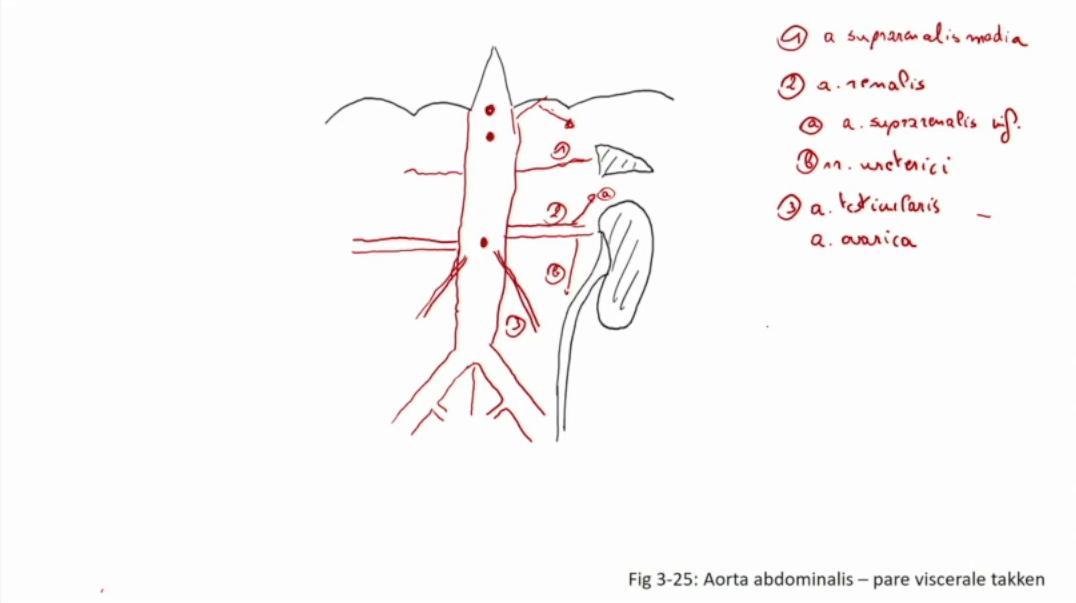

Fig 3.25: Aorta abdominalis - pare viscerale takken

|

|